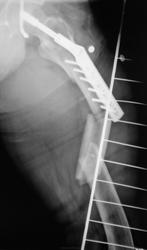

- https://radiomed.ru/sites/default/files/styles/case_slider_image/public/user/12/13.p2070034.jpg?itok=UmusZMq4

Вы правы..., сейчас металлоостеосинтез будет проблемен.

красиво!!! DHSку теперь придется убрать, а вот что поставить? Ну может PFN, интрамедуллярный стержень с дополнительной фиксацией шейки. С б/берцовой проще, перелом благодатен для интрамедуллярного остеосинтеза.